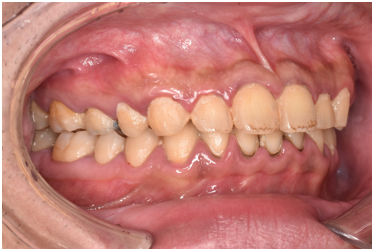

general 20代男性「歯周病治療と歯石を除去したい」中等度の歯周炎に歯石除去と歯周病治療を行った症例

| 行ったご提案・治療内容 | 初診時に撮影したレントゲン、口腔内写真、歯周病検査の結果を用いて、歯周病治療の必要性をお伝えしました。 初診時は歯ブラシの使い方などセルフケアの方法をご説明し、その後に歯肉縁上歯石(歯肉より上に付く黄色または乳白色の歯石)を除去しました。 歯肉の炎症がある程度落ち着いた後日、再評価を行い、歯周治療へ移行しました。 |

| 術後の経過・現在の様子 | 経過は良好です。 |